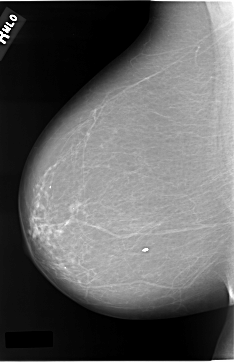

C_0037_1.LEFT_MLO

LEFT_MLO LINES 5816 PIXELS_PER_LINE 3824 BITS_PER_PIXEL 12 RESOLUTION 50 OVERLAY